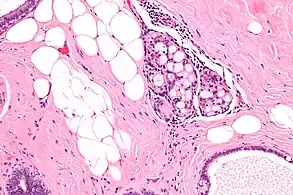

| Micrograph of collagenous spherulosis with the characteristic histomorphology - intratubular eosinophilic material with a spoke-like arrangement. H&E stain. | |

Collagenous spherulosis is characterized by a tubular/cribriform architecture with intratubular eosinophilic material that classically is arranged like the spokes of a wheel ("radial spikes"). There is usually no mitotic activity, and two cells populations (epithelial & myoepithelial) are present, like in benign breast glands.

The lesions are typically small (less than 50 spherules per lesion, less than 100 micrometers in size) and may be multifocal.